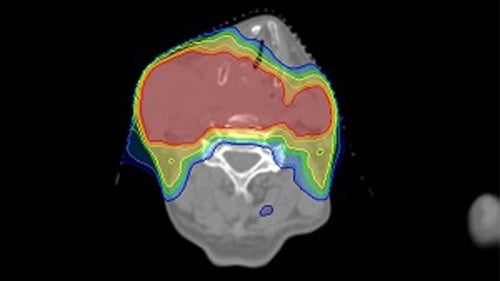

咽頭がんや喉頭がんなど主に頸部に発生するがんです。手術が困難なことや、術後の後遺症が大きいことなどから放射線治療の適応となることが多い疾患です。頭頸部には視神経・視交叉、脳幹、脊髄、耳下腺、下顎骨などの重要な臓器が密集しており、従来の治療では重篤な副作用が出現したり治療効果が落ちたりといったことが生じやすい領域でした。IMRTにより、重要臓器を極力さけながら病変部に十分な放射線量を投与することが可能となりました。副作用は頸部の広範囲の皮膚炎や粘膜炎による疼痛、唾液腺障害による唾液分泌低下、味覚障害、顎骨壊死など多岐にわたります。(図:頭頸部がんに対するIMRT)

原発性脳腫瘍は主に手術後の術後照射の適応となります。腫瘍の部位だけでなくその周囲も再発リスクが高いため、広範囲の照射となるケースが多くなります。頭頚部同様に近くに眼球や水晶体、視神経、脳幹といった重要臓器があるため、IMRTがよい適応となります。治療は30回程度が標準です。副作用は局所の脱毛、頭痛、気分不快、白質脳症、放射線脳壊死などがあります。(図:原発性脳腫瘍に対するIMRT)